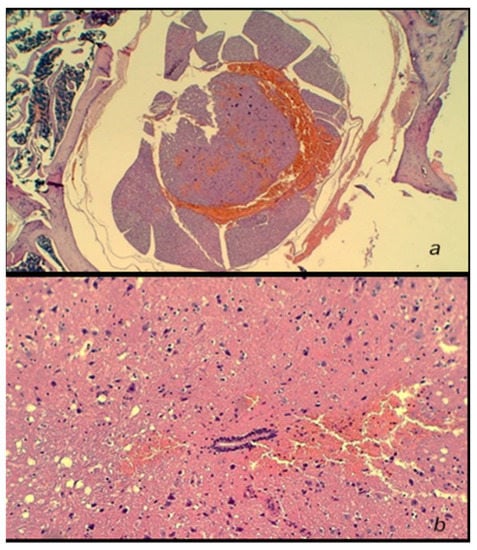

3.2. Microscopy

3.2.1. Early Post-Injury Course, Immediate Effect

3.2.2. Delayed Post-Injury Course, Immediate Effect

3.2.3. Delayed Post-Injury Course, Long-Term Effect